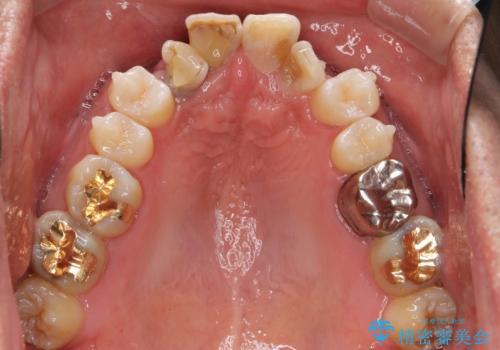

奥に引っ込んでいる歯をセラミックでかぶせたい 補綴前矯正 50代男性

- 神経が死んでいる前歯2本(右上21)をセラミッククラウンでかぶせたいとご希望され、来院された患者様です。

歯並びにより、そのままだときれいに被せ物をいれられない状態でした。

補綴前矯正としてマウスピース矯正(インビザライン)を行った後、セラミッククラウンによる補綴治療を行いました。

患者様の「できるだけ短期間で治療を終わらせたい、セラミックが入れられたら良いので大がかりなことはしたくない」とのご要望により、3Dシミュレーションを何度も行い患者様とのコンサルを重ね、上顎左右犬歯と左下2を抜歯して②のプランである補綴前矯正(インビザライン)を行うことにしました。